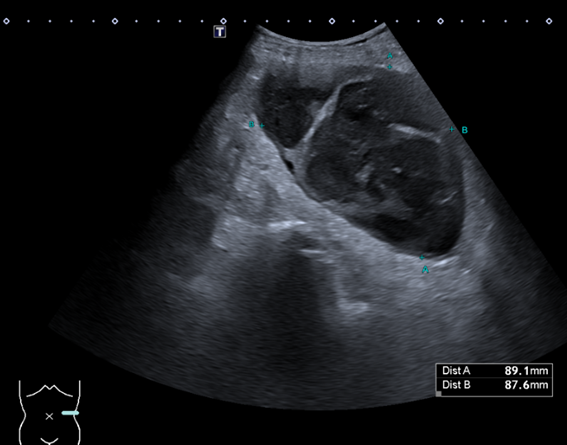

Ante la persistencia de los síntomas, se realiza ecografía en Atención Primaria, identificándose una lesión ovalada de unos 9 cm adyacente al riñón izquierdo, heterogénea, con áreas quísticas y sin flujo Doppler. La revisión de imágenes antiguas revela un quiste simple de gran tamaño en la misma localización, por lo que se sospecha complicación del mismo. Se deriva a Medicina Interna para estudio.